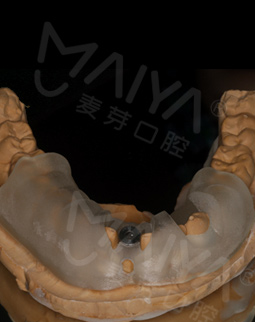

经过数字化的拍片检查后发现,我的牙周情况还是蛮不错的,可以用MAC数字化精确种植牙实现8分钟种稳一颗牙,而且工作人员说我可以作为直播案例主角分享自己的故事,感到非常荣幸。

在种牙之前,这里的硕博专家给我讲解了种植牙的相关知识,而且通过数字化的设备模拟出种牙的全过程,打消了我的种种疑虑。专家说,随着数字化在口腔领域的应有,种牙已经不像之前那样等待时间长、创口大、步骤多,而是实现即种即用,并且利用数字化导航设备种牙更精确,不用仅仅依靠医生经验去进行种牙,手术前一周我已经做了取模,今天准备种牙!